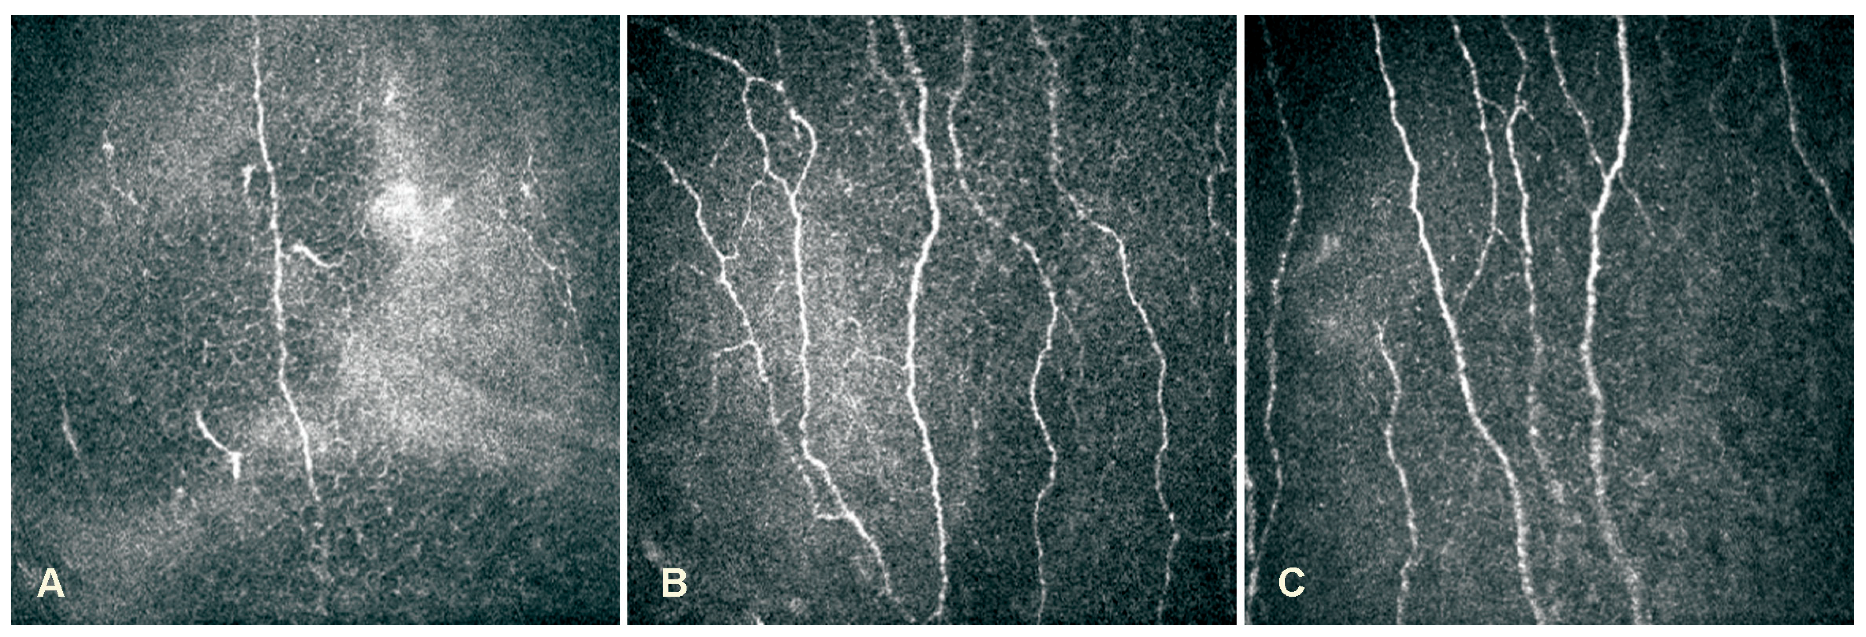

Corneal Sub-Basal Nerve Changes in Patients with Herpetic Keratitis during Acute Phase and after 6 Months

- Patel, D.V.; McGhee, C.N. Contemporary in vivo confocal microscopy of the living human cornea using white light and laser scanning techniques: A major review. Clin. Exp. Ophthalmol. 2007, 35, 71–88. [Google Scholar] [CrossRef] [PubMed]

- Patel, D.V.; McGhee, C.N. In vivo confocal microscopy of human corneal nerves in health, in ocular and systemic disease, and following corneal surgery: A review. Br. J. Ophthalmol. 2009, 93, 853–860. [Google Scholar] [CrossRef] [PubMed]